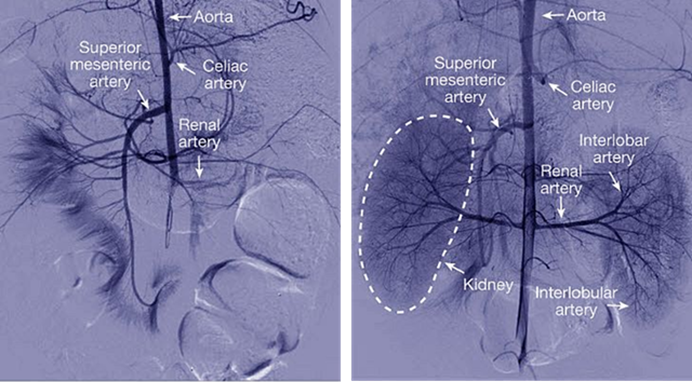

图3 ECMO(左图)和OrganEx(右图)灌注3小时后的猪肾脏。(图源:[2])

注:黑色表示液体到达的位置